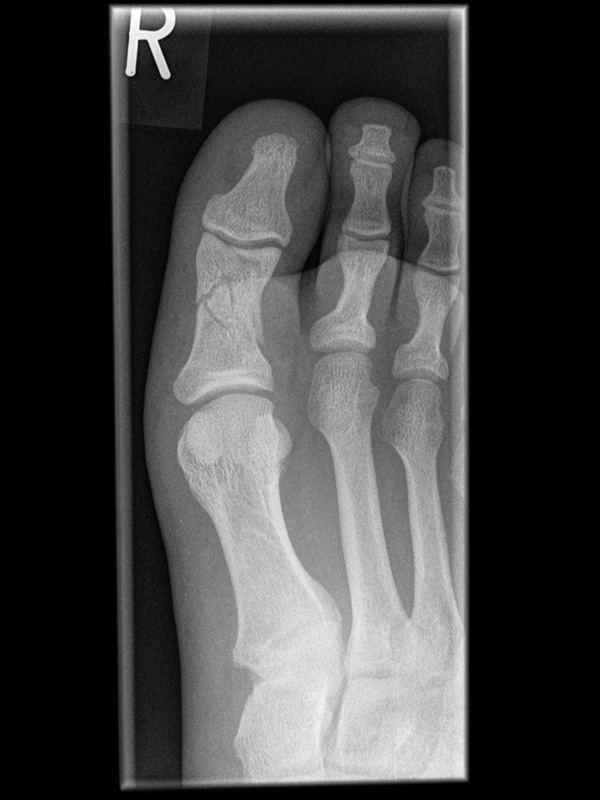

Besondere Bemerkungen zum Beispielbild:

• Verlaufskontrolle nach korrigierendem Vorfußeingriff bei Riesenwuchs des 2. Strahls mit verdicktem Os metatarsale II.

• Z.n. Amputation des Zehenendglieds D2.

• Z.n. Weil Osteotomie des Os metatarsale II.

• Hallux valgus interphalangeus.

Zur Vollansicht und zum Lesen der Bildbeschreibung bitte die Bilder anklicken.